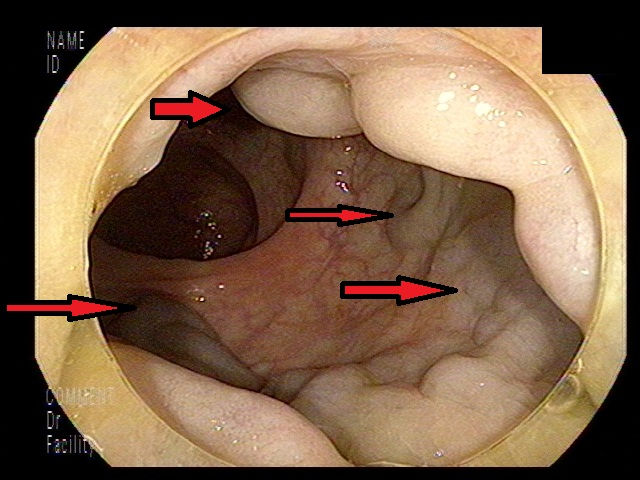

그리고 대장에서 간으로 혈액을 운반하기 위해 문맥이라고 부르는 큰 정맥의 압력이 상승해서 대장에서 간으로 혈액을 수어긋나는 문맥이라고 호출하는 큰 정맥의 압력이 높게되 문맥압 항진증, 림프가 림프절 바깥으로 새어 나오는 경우도 있고요. 이것들이 복부에 새어 나오면 복수가 되어버립니다.

간경변증이 가득히 진행한 차후엔 거의 합병증 형태로 출현하고 이 경우를 ‘비대상성 간경변증’이라고 합니다. 식욕 부진, 소화불량, 복부의 불쾌감 등 비색다른적인 증상이 간경화 증상으로 일어날 수 있어요. 복수가 차면 복부의 팽만감과 하지 붓기가 등장하고 심지어 숨이 차기도 합니다. 또한 식도와 위 정맥류가 발생해 심하게는 출혈할 수 있어요.